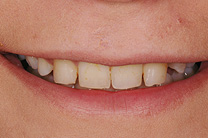

Gesamtrekonstruktionen

Fehlen in einem Kiefer alle Zähne oder sind die meisten Zähne in einem schlechten, nicht erhaltungswürdigen Zustand, ist es sinnvoll eine Gesamtrekonstruktion anzufertigen. Diese kann sowohl dental als auch implantat-getragen sein. Die Gesamtrekonstruktionen sind zeitlich wie finanziell aufwendig, bestechen aber durch ihre Ästhetik und die Langlebigkeit. Der Vorteil ist, dass viele kleine Arbeiten und Reparaturen in den nächsten Jahren wegfallen werden.